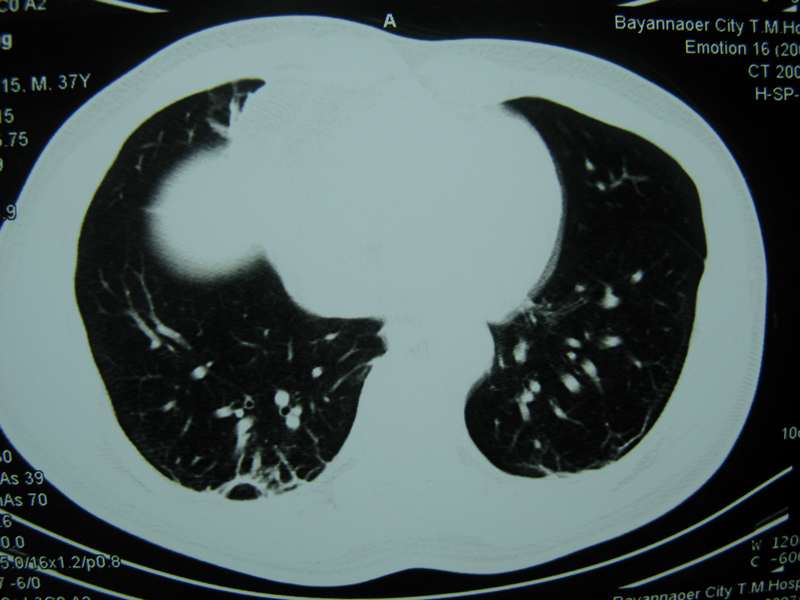

男,37岁,主述胸疼厉害,无咳嗽,无发热,血象也不高,病灶内ct值脂肪密度,右侧胸腔内少量积液,同道们考虑什么?谢谢!

脂肪垫,右下肺感染,少许积液是症状所在

纵膈脂肪堆积,右肺慢性炎症。

两肺下叶基底段纤维灶,右肺下叶基底背侧相应胸膜肥厚,右肺中叶内侧段部分不张。前中下纵隔团块状脂肪影,随访除外胸腺脂肪瘤。

纵膈脂肪堆积,右肺慢性炎症